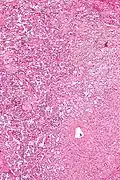

Intermed. mag.

Intermed. mag. -

A gangliocytic paraganglioma is a rare tumour that is typically found in the duodenum and consists of three components: (1) ganglion cells, (2) epithelioid cells (paraganglioma-like) and, (3) spindle cells (schwannoma-like).[1]

GP consist of three components (1) ganglion cells, (2) epithelioid cells (neuroendocrine-like), and (3) spindle cells (schwannoma-like). The microscopic differential diagnosis includes poorly differentiated carcinoma, neuroendocrine tumour and paraganglioma.[1]